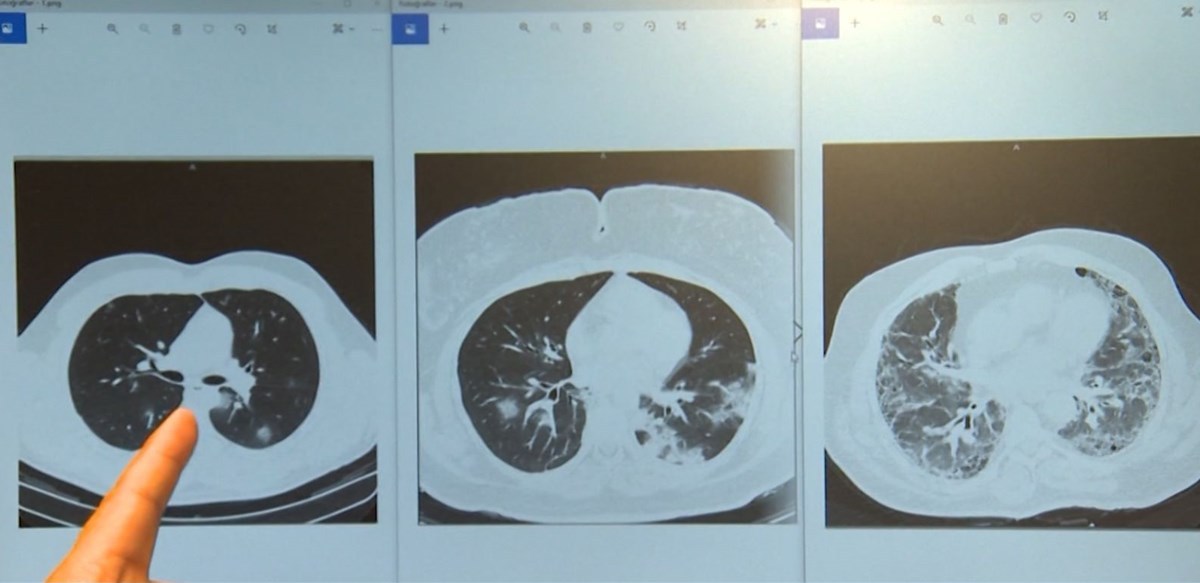

Kovid-19 salgınında hastanelerin yoğun bakımları aşı olmayan hastalarla dolu. Göğüs Hastalıkları Uzmanı Profesör Doktor Muhammed Emin Akkoyunlu, hastanede yatan 3 korona hastasının röntgenleriyle son durumu anlattı. Röntgenler, aşılı ve aşısız kişilerde hastalığın nasıl seyrettiğini gözler önüne seriyor.

Üç ayrı hasta, üçü de 60 yaş üzeri, üçü de erkek, farkları ise sadece aşı. İki doz aşı olan hasta ayakta tedavi ediliyor. Bir doz aşı olan serviste, hiç aşı olmayan ise yoğun bakımda.

İlk filmde 2 doz aşı yaptırdıktan sonra ailesi kovid-19 olan bir hastanın kendisi de kovid-19 hastası ve ayakta tedavi ediliyor. Görüntüdeki siyah alanlar normal akciğer alanlarını gösteriyor. Sadece sağ alt köşede hafif bir beyazlık var ve kovid-19 unsurunu görüyoruz.

İkinci filmdeki hasta ise serviste yatıyor. Üçüncü filmdeki hasta ise yurt dışından geldi ve hiç kovid-19 aşısı olmadı. Neredeyse tamamen akciğerlerinin virüsle kaplandığını görüyoruz. Yani ölüm riski oldukça yüksek. Toparlasa bile akciğerlerde hasar kalma ihtimali bulunuyor.